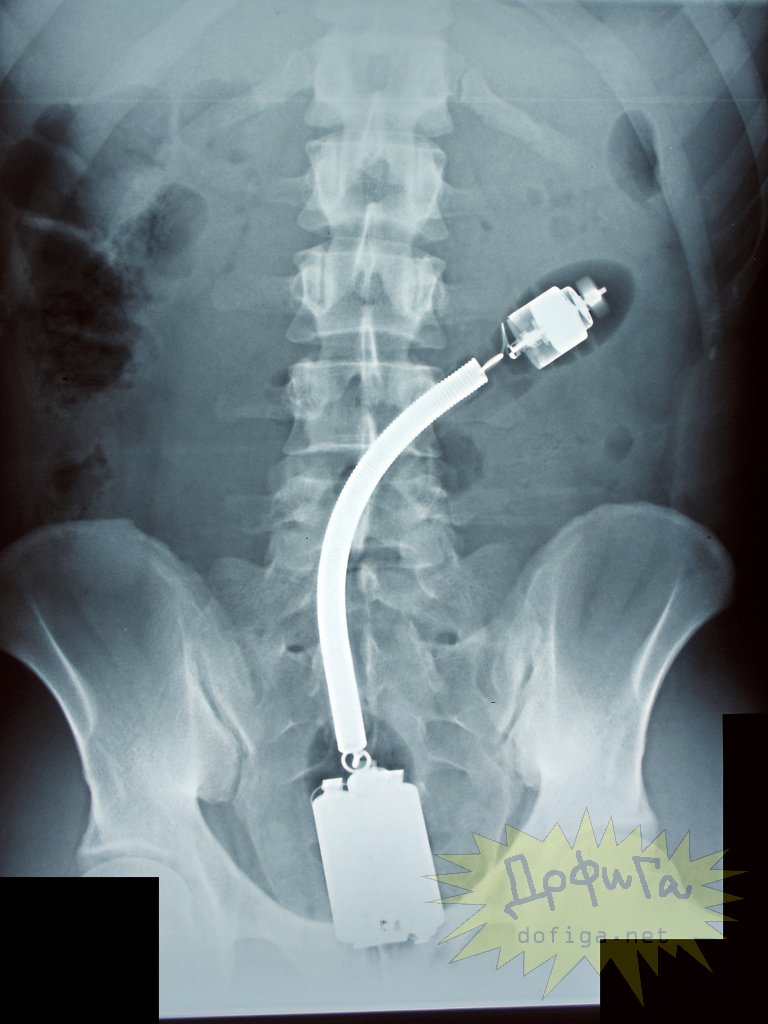

アナルに ”何かしら” を突っ込んで取れなくなってしまう人たちは意外に多いみたいで、そんな人たちのレントゲン写真を集めたギャラリー[13]images